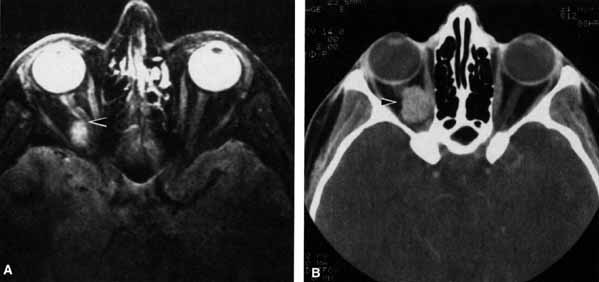

Fig. 6 T2-weighted magnetic resonance imaging (MRI) shows cerebrospinal fluid (CSF) surrounding the optic nerve within the subarachnoid space (arrow). The CSF extends to the posterior pole of the globe. An optic nerve meningioma is present on the contralateral side.

The optic nerve remains vulnerable to compression within the bony confines of the orbit. Compressive optic neuropathy is most likely to occur where the optic nerve is tethered to the bone, that is, at the orbital apex (Fig. 7A). The optic nerve in other areas of the orbit can be displaced markedly without suffering vision loss (Fig. 7B).